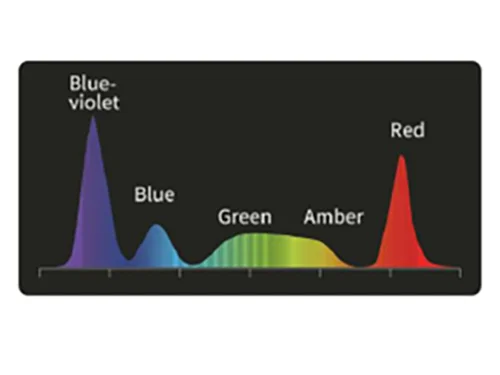

PSI: Спектральная визуализация цветовой палитры полихроматическая визуализация

Выравнивает пропорции узкополосного фиолетового и красного цвета на основе белого цвета и использование алгоритмов сложения для повышения цветового контраста.

Применение

- Повышение вероятности обнаружения поражений, таких как воспаление, атрофия, рак на ранних стадиях, полипы и иные поражения при среднем и слабом увеличении и повышение эффективности обследования.

Белый свет

PSI